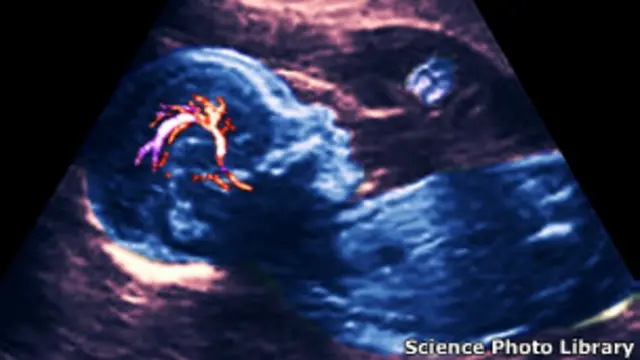

Fuente de la imagen, Science Photo Library

1 de cada 4 embarazos

Según la Asociación del Aborto Espontáneo de Reino Unido, uno de cada cuatro embarazos acaba en un aborto espontáneo, y sin embargo la mayoría de las mujeres nunca habla sobre el tema.